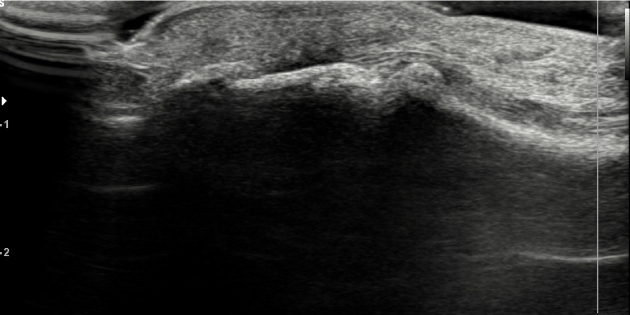

거대 세포종의 모습

거대 세포종 증상

통증과 압통은 없으나 신경, 혈관 쪽에 엉키면 후에는 수술도 어렵기 때문에 조기 발견하여 치료하는 것이 중요합니다.